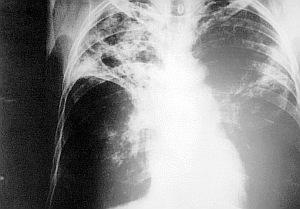

TB im Röntgen: Künftig reicht Batterie-betriebener Tester (Foto: Wikimedia) |